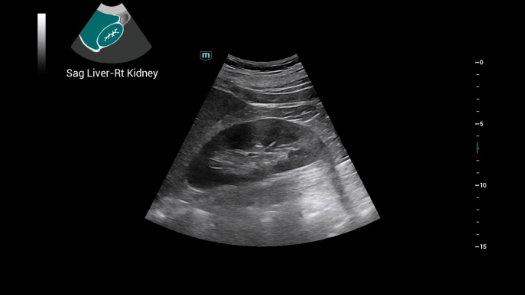

Dise?ado especĂficamente para usuarios de atenciĂłn primaria, el equipo Consona presenta soluciones nuevas y concretas que lo ayudan a realizar diagnĂłsticos sin problemas y de manera eficiente en diversos tipos de pacientes.

Independientemente de si lleva a cabo su rutina en hospitales o clĂnicas, o si estĂĄ perfeccionando sus habilidades en aplicaciones de diagnĂłstico por imĂĄgenes generales, atenciĂłn de la salud de la mujer o especialidades cardiovasculares, esta serie dispone de herramientas muy potentes para que se mantenga a la vanguardia.